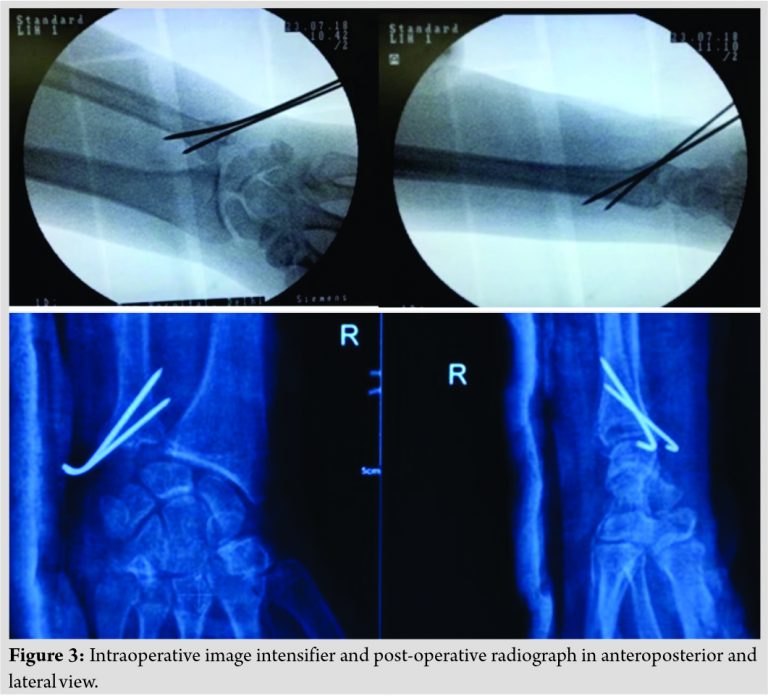

We managed it with closed reduction and internal fixation with K-wire on an emergency basis under regional anesthesia and kept in an above elbow forearm brace (Fig. 3).

The procedure followed during reduction was sustained traction, and 1.8 mm K-wire was placed temporary and used as a simple joystick to reduce the fractured head part with and 2 K-wires of size 2.0 mm were inserted volarly under C-Arm guidance. In the follow-up at 4 weeks, K-wire was removed as an outpatient procedure and a below-elbow cast was given, and forearm rotation was started and brace was kept for further 2 weeks (Fig. 4).